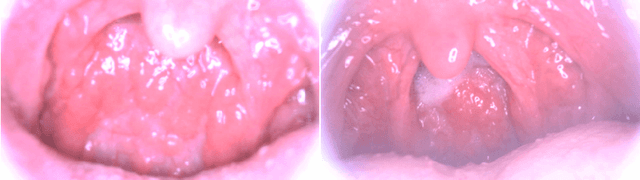

Abstract:Medical images have been indispensable and useful tools for supporting medical experts in making diagnostic decisions. However, taken medical images especially throat and endoscopy images are normally hazy, lack of focus, or uneven illumination. Thus, these could difficult the diagnosis process for doctors. In this paper, we propose MIINet, a novel image-to-image translation network for improving quality of medical images by unsupervised translating low-quality images to the high-quality clean version. Our MIINet is not only capable of generating high-resolution clean images, but also preserving the attributes of original images, making the diagnostic more favorable for doctors. Experiments on dehazing 100 practical throat images show that our MIINet largely improves the mean doctor opinion score (MDOS), which assesses the quality and the reproducibility of the images from the baseline of 2.36 to 4.11, while dehazed images by CycleGAN got lower score of 3.83. The MIINet is confirmed by three physicians to be satisfying in supporting throat disease diagnostic from original low-quality images.